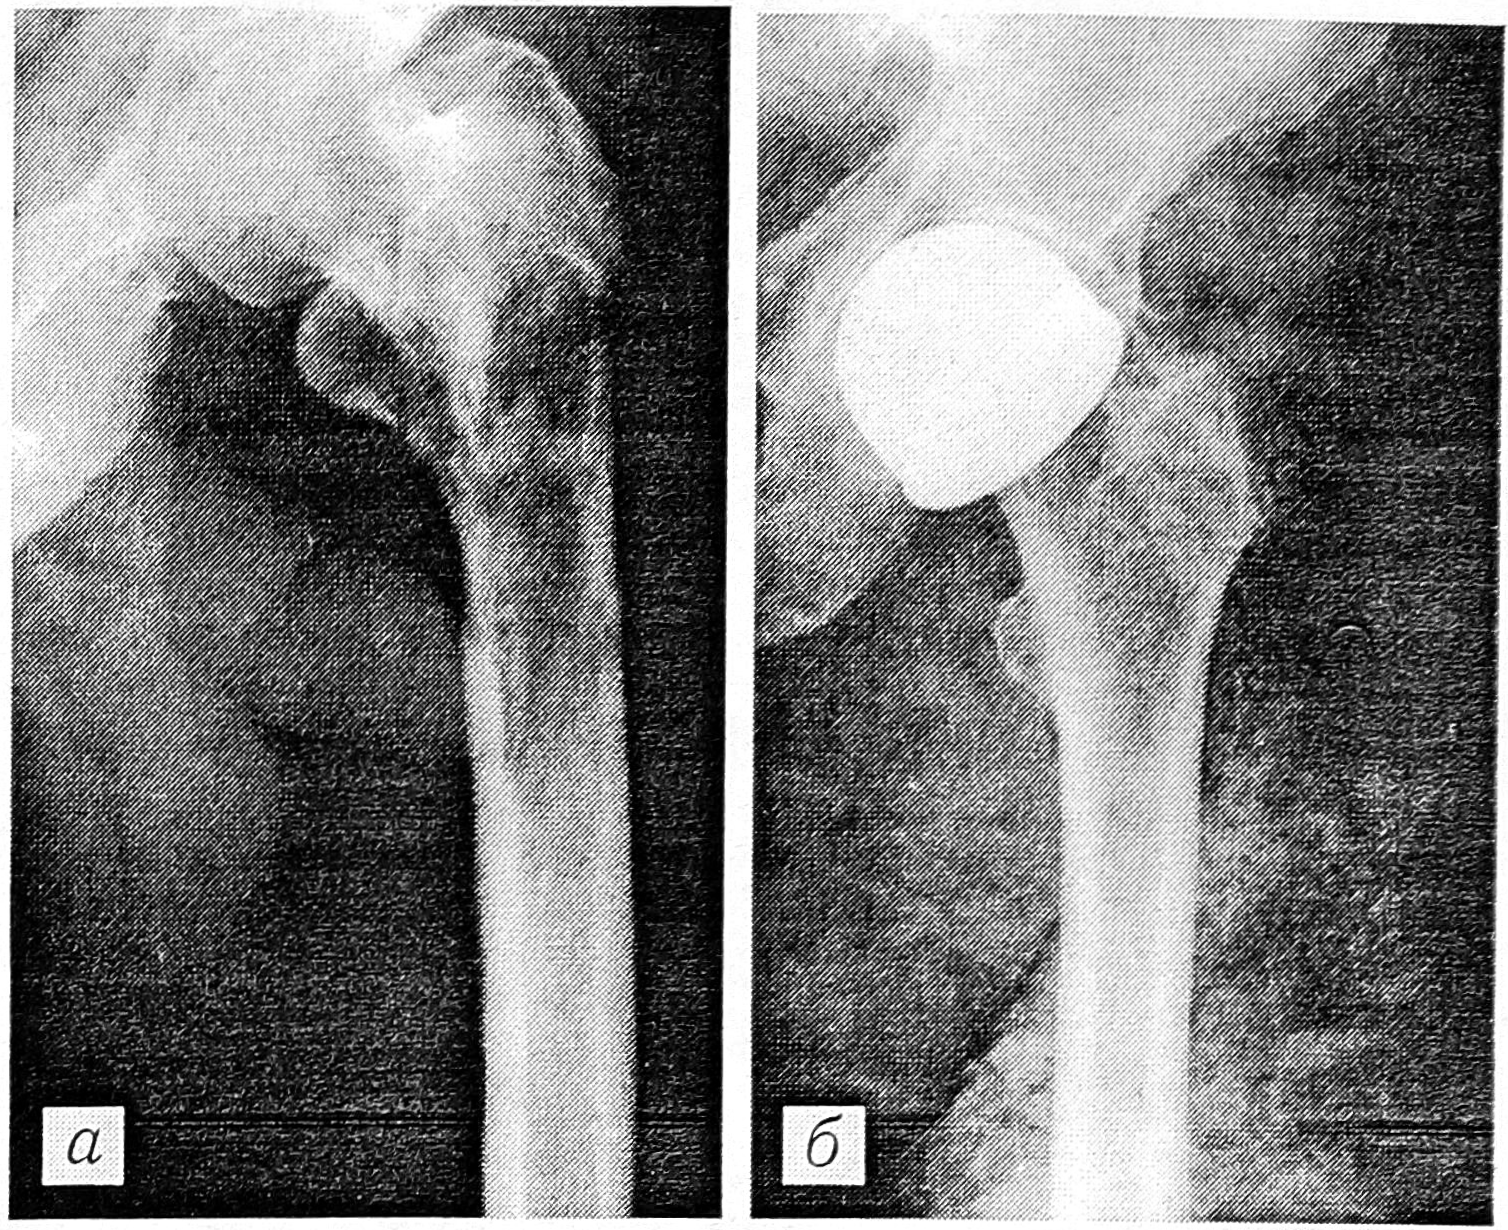

Первая такая операция — тотальное удаление плечевой кости у больного с ретикулоклеточной саркомой — в ЦИТО произведена 10.03.67 Н.Е. Махсоном. Дефект замещен аналогичным по форме консервированным холодом аллотрансплантатом. Трансплантат был немного длиннее удаленной кости и кожа над его дистальным отделом была несколько натянута, но функция руки в локтевом суставе оказалась удовлетворительной (движения в нем составляли от 180 до 90°, движения в плечевом суставе — в пределах 45°). В 1968 и 1969 гг. Н.Е. Махсоном оперированы 2 больных с хондросаркомой бедренной кости. У одного из них аллотрансплантат удалось подобрать по форме и размерам почти идеально. Функция бедра у этого пациента была вполне удовлетворительной (рис. 1). У второго больного аллотрансплантат оказался значительно меньших размеров. Приводим краткую выписку из его истории болезни.

Рис. 1. Рентгенограмма больного П. после тотального удаления бедренной кости с замещением дефекта консервированным аллотрансплантатом и функция оперированной ноги.

Больной У., 57 лет, в течение 3 лет получал физиотерапию и санаторно-курортное лечение по поводу предполагавшегося «полиартрита». При обследовании в ЦИТО обнаружена опухоль проксимальной половины левой бедренной кости, на рентгенограммах выявлены обширный очаг деструкции с большим мягкотканным компонентом, патологический перелом в подвертельной области (рис. 2, а). 23.07.69 произведена операция: тотальное удаление бедренной кости с замещением дефекта аллотрансплантатом. Поскольку головка трансплантата имела меньший размер, на нее был надет металлический колпачок (рис. 2, б). В последующем у больного сформировался свищ в верхнем отделе раны. Проведена санация протеолитическими ферментами, свищ закрылся и больше не открывался. Морфологическое исследование опухоли: веретеноклеточная саркома. В дальнейшем у больного отмечалось рассасывание аллотрансплантата. Ходит с опорой на костыль и трость. Через 27 лет признаков рецидива и отдаленных метастазов нет.

Рис. 2. Рентгенограммы больного У.: a — до операции; б — после тотального удаления бедренной кости и замещения дефекта консервированным аллотрансплантатом (трансплантат не соответствует по размеру удаленной бедренной кости, на головку бедра надет металлический колпачок).